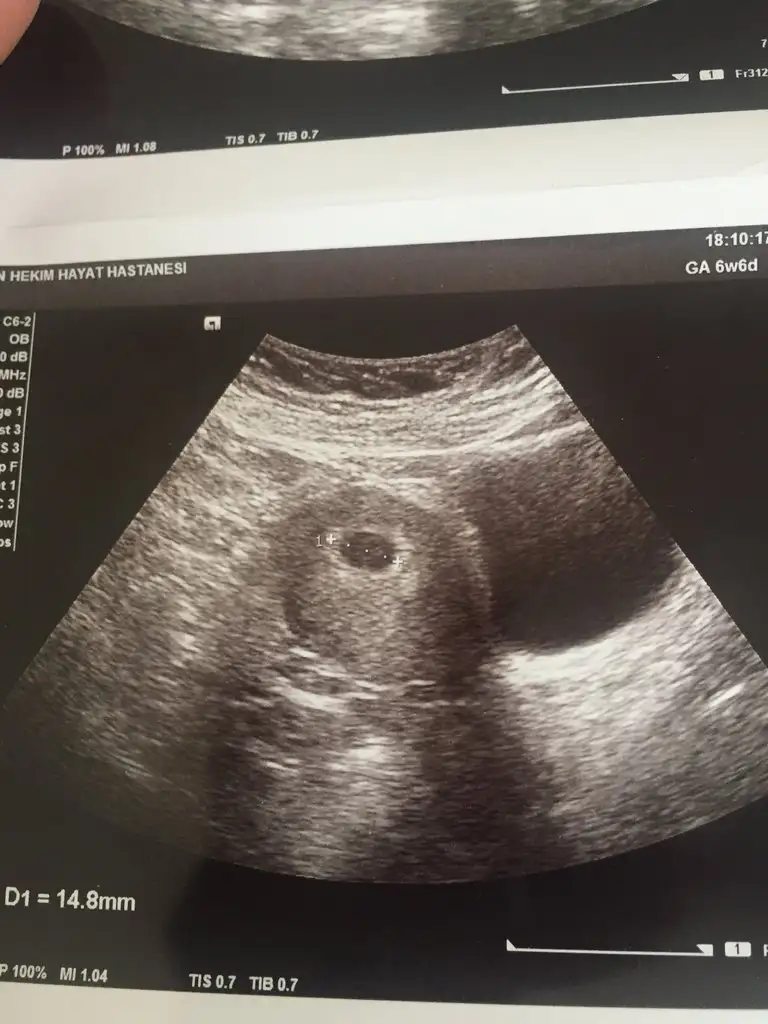

Mrb dün 5+5 günlük karından usg çekildi bi bana da yorum yapar mısınız